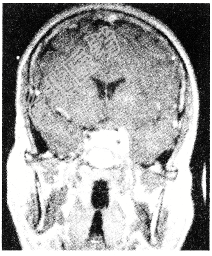

- 单项选择题有关脑膜瘤(如图所示),以下哪项说法不恰当

A、脑膜瘤多发源于软脑膜细胞

B、多数脑膜瘤为良性肿瘤,但有少数脑膜瘤在病程中发生恶性变

C、膜瘤发病率居颅内肿瘤的二位

D、多发生于旁矢状面和凸面

E、一般男女发病率之比约为1:2